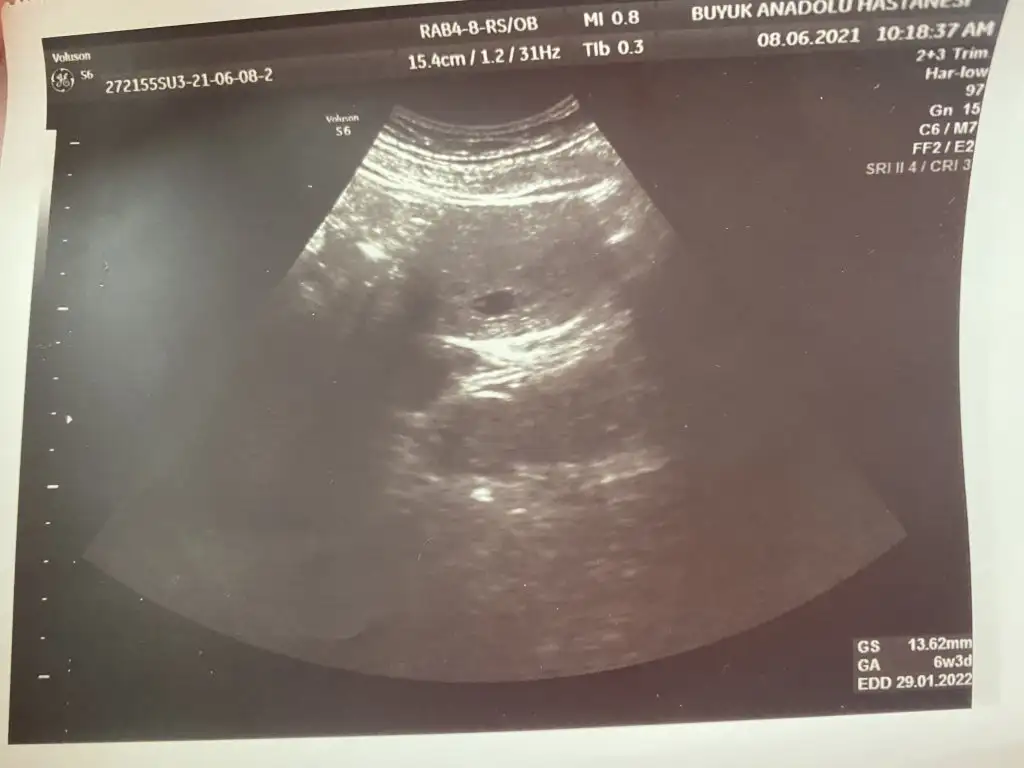

Merhaba ben 15 Nisanda kürtaj oldum.Adet olmadan kürtajdan 40 gün sonra hamile olduğumu öğrendim 25 Mayısta kese karından görünmedi alttan bakınca doktor yeni oluşan bi kese olduğunu düşündü 28 mayısta karından keseyi gördü.Keseye göre 5 hafta dedi.(5 hafta olma imkanı yoktu ama adet tarihine göre hesaplamadan dolayı 2 hafta fazla gibi hesaplandığından galiba ) 2 hafta sonra gel kalbine bakalım dedi.İlk hamileliğimde 6+2 de bebeğin kalbi durmuştu bende dayanamadım 11 gün sonra (8 Haziranda) 6+4 olması gereken zamanda özele gittim. Doktor henüz kesenin küçük olduğunu 20 mm olduğunda kalp atışının duyulduğunu söyledi.Keseye göre 6+3 tü bir güne takılmadım cihazdan da farkedebilir.Bebek çok küçük bir nokta şeklindeydi tutunmuş dedi. 2-3 hafta sonra gel dedi kalp için. 1 hafta geçtikten sonra ben devlete gittim. Kendi göründüğüm doktorun işi çıkmış gitmiş. Başka bir doktora göründüm ama o doktora hiç güvenmiyorum baktı daha kalp atışı yok 2 hafta sonra gel dedi kaç haftalık göründüğünü sordum 5+6 dedi (normalde 7. Haftada olması lazım) durumu anlattım bir hafta öncesinde 6+3 dendiğini doktor benim cihazımda ben bu şekilde ölçtüm 2 hafta sonra gel demekten başka bir şey söylemedi. Tabi haftasını o şekilde söyleyince ben kafamda bitirdim yine kalbi durdu diye düşündüm.O günden sonra kahverengi lekelenme başladı akıntının içinde kan görünce ben bebeği düşüreceğimi düşündüm korktum. Devletteki diğer doktor gelmişti ona gittim durumu anlattım baktı kese düzgün görünüyor dedi. Özelde çok küçük bi noktada olan bebek daha belirgin görünüyordu bu sefer Keseye göre değil de bebeğe göre ölçtü 6+1 çıktı 2 gün önceki ile de uyumluydu ama önceki haftalarla uyumlu değil. Kalp atışı yine yoktu.Kendimce düşünüyorum diğerlerinde Keseye göre ölçülmüştü şimdi bebeğe göre ölçüldüğü için mi acaba diyorum ama kese 8 haziranda da 17 haziranda da 13 mm idi. Kese gelişmeden bebek gelişir mi anlamadım. Doktor progestan verdi 1 hafta sonra gel dedi dinlenmemi bol su içmemi ilişkiye girmememi söyledi. Progestanı kullanıyorum ama acaba ölü bebeği mi karnımda tutuyorum ilaç kullanarak diye düşünüyorum.Güvenmediğim doktor hariç ultrason görüntülerini vermişti aşağıya ekledim birisi hariç diğerleri devlet. Bu konuda bilgisi olan benzer durum yaşayan yardımcı olur musunuzBen zaten kötüyü kabullendim gerçek neyse onu öğrenmek istiyorum